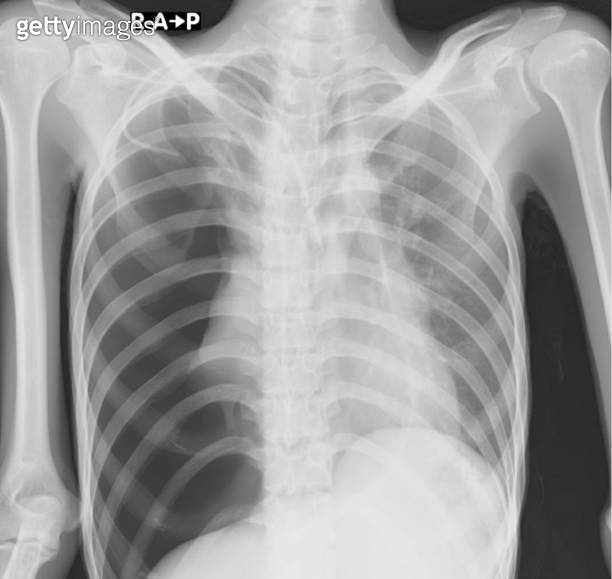

Pneumothorax Chest X Ray Expiration . chest radiography for pneumothorax screening is a frequently employed test. — a tension pneumothorax occurs due to the progressive accumulation of intrapleural gas in thoracic cavity caused. — primary spontaneous pneumothorax that does not cause respiratory or cardiac symptoms can be. However, there is some controversy about. on an expiratory film, a pneumothorax will appear relatively larger, taking up a larger percentage of the thoracic cavity. The pleura is pushed further away. — when a suggested pneumothorax is not definitively observed on an inspiratory film, an expiratory film may be helpful. right sided spontaneous pneumothorax.